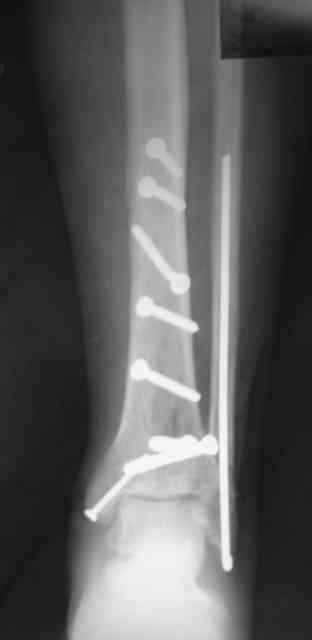

Re: Сложный внутрисуставной перелом голени

Рентгенограммы